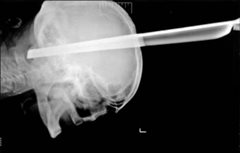

ΑΠΙΣΤΕΥΤΟ – Επέζησε, έχοντας καρφωμένο στο κεφάλι ένα μεταλλικό πόδι από σκαμπό

Σερβία